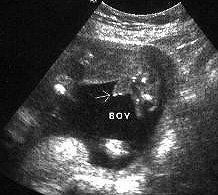

الأسبوع ال18